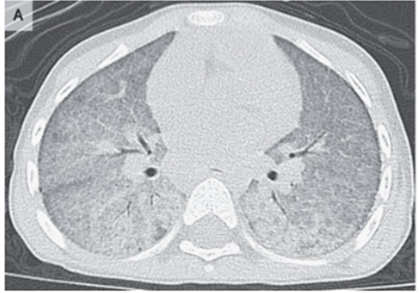

特発性肺ヘモジデローシス

3歳女性。発熱、低酸素。

Hb 5.3、CTではびまん性すりガラス陰影・気管支の牽引性拡張を認めていた。

気管支肺胞洗浄が施行され、赤みがかかったピンク色であり、細胞学的検査によりヘモシデリンを含むマクロファージを認めた。

特殊採血の結果、感染症やリウマチ性疾患、先天性心疾患を含めたびまん性肺胞出血の関する評価は陰性であった。

上記より特発性肺ヘモジデローシスと診断された。

特発性肺ヘモジデローシスは「喀血」「貧血」「胸部異常陰影」が三徴候だが、小児の場合は「喀血」が無いことがあるため注意。